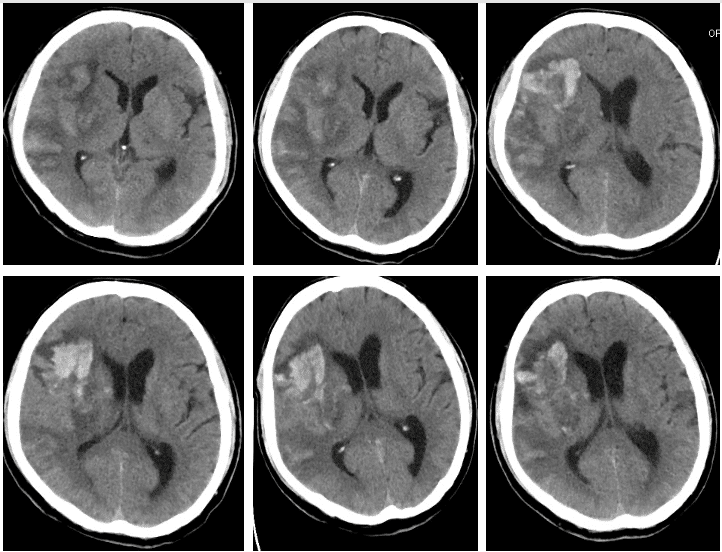

动态复查头CT(2023-09-16 ~ 2023-10-12)可见右侧半球大面积梗死区域由条状密度影(梗死后出血转化1型)逐渐转变为较局限片或块状高密度影(梗死后出血转化2型),其后可见逐步吸收转归变化。

初次CT检查已发现右侧半球大片状低密度,监护提示阵发性房颤,鉴于抗凝治疗更高的出血风险,给予小剂量抗血小板治疗(ASP 100mg> Qd),数日后患者出现头痛及嗜睡状态,动态复查CT提示出血转化加重,遂停用抗血小板治疗,临时给予氨基己酸止血及甘露醇脱水处理。随后,梗死区域内血肿逐渐吸收,意识水平正常、头痛缓解,好转出院。3月内动态观察病情变化,出院3月后考虑启动抗凝治疗。